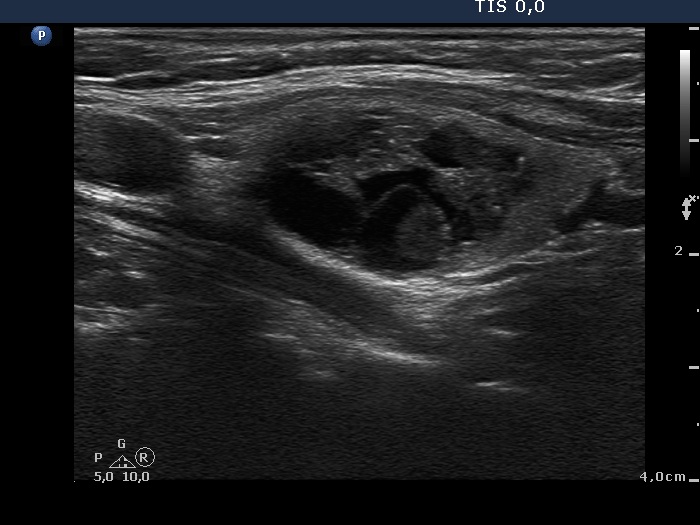

First examination (ultrasonographic picture 4)

Left lobe, another longitudinal scan. In this section we can reveal intranodular hyperechogenic lines dorsal to cystic areas, therefore these intranodular hyperechogenic figures are caused by back wall posterior enhancement.